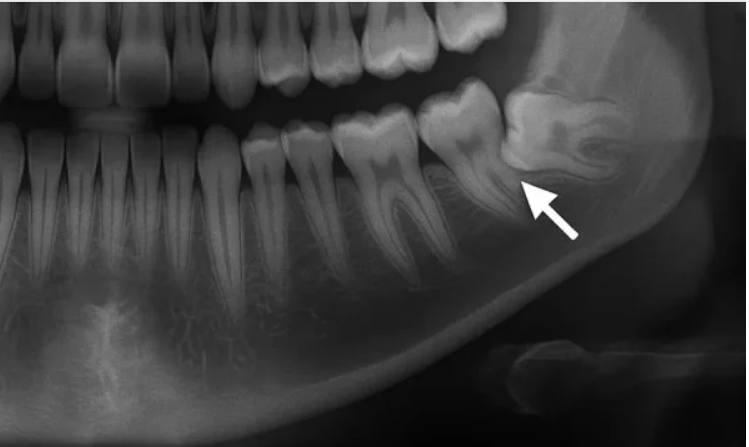

② 隣の歯の寿命を縮めている(最も危険なケース) 親知らずが斜めに生えていると、手前の大切な歯(7番目の歯)との間に深い隙間ができます。ここに汚れが溜まると、親知らずだけでなく、手前の健康な歯まで「深いむし歯」や「重度の歯周病」にしてしまいます。手前の歯を守るために、親知らずを抜くという選択は非常に重要です。

③ 歯並びに悪影響を及ぼしている 横向きに埋まっている親知らずが手前の歯をグイグイと押し続け、結果として全体の歯並びを乱してしまうことがあります。

通常のデジタルレントゲンだけでなく、必要に応じて歯科用CTを使用します。

親知らずの根っこが顎の重要な神経や血管とどのくらい近いのかを3次元的に確認することで、偶発的な事故を防ぎ、安全でスムーズな処置を計画します。